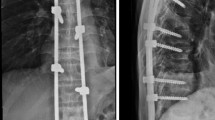

Median time from first surgical consultation to surgical intervention was 9 (range 0–377) days. The most commonly treated areas were the thoracolumbar (T10–L2, n = 39) and thoracic (n = 38) regions, followed by the lumbar (n = 22) and lumbosacral (L4–S2, n = 2) regions. The median operating time was 122 (range 57–325) minutes; median blood loss was 100 (range 50–500) ml based on data available for 41 patients. Five or more vertebral bodies were bridged in 65 patients (64 %), four in nine patients (9 %), and three in 27 patients (27 %). Vertebroplasty was performed in six patients (6 %), kyphoplasty in 10 patients (10 %), and vertebral body stenting in 19 patients (19 %). Cement augmentation of pedicle screws was performed in three patients (3 %).

A wound-healing disturbance occurred in four patients; two of these were deep wound infections. Four patients experienced construct failure; two patients had a pedicle screw pullout, with one of the two patients requiring a reoperation; and one patient had a broken pedicle screw (S1), causing pain and requiring reoperation 1.5 years after the index surgery. In one patient, secondary screw pullout occurred as a result of tumor progression, which required revision surgery within 1 month of the index surgery. After the second surgery, the patient developed a superficial wound infection and experienced neurologic deterioration due to tumor growth into the spinal canal; neither preoperative nor postoperative radiotherapy was administered. Local tumor progression was also the cause for neurologic deterioration in two other patients, both within 4 months after index surgery. Neurologic deterioration also occurred in two other patients; one experienced permanent complete paraplegia resulting from medial placement of a pedicle screw, and revision surgery was performed without postoperative neurologic improvement. Cement extravasation resulting in an incomplete spinal cord lesion (ASIA C), from which the patient recovered fully (ASIA E) after reoperation, was the cause in the other patient. A total of six patients (7 %) required revision surgery. One patient experienced transient neurologic deterioration immediately after surgery at the recovery unit but recovered spontaneously within 6 h. Neurologic status over time is displayed in Table 4.